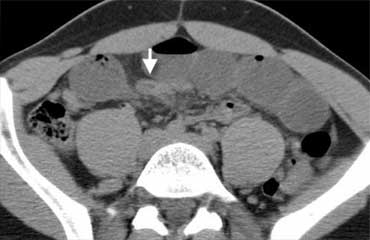

Viêm hạch bạch huyết mạc treo ruột.

Viêm hạch bạch huyết mạc treo ruột là bệnh lý thường hay bị nhầm lẫn với viêm ruột thừa.

Đây là nguyên nhân phổ biến thứ hai gây đau hố chậu phải sau viêm ruột thừa.

Bệnh được định nghĩa là tình trạng viêm lành tính, tự giới hạn của các hạch bạch huyết mạc treo ruột bên phải mà không có quá trình viêm nền tảng có thể xác định được, xảy ra ở trẻ em nhiều hơn người lớn.

Chẩn đoán này chỉ có thể được xác lập một cách chắc chắn khi tìm thấy ruột thừa bình thường, vì bệnh lý hạch cũng thường gặp trong viêm ruột thừa.

Dấu hiệu chính: Hạch to kèm ruột thừa bình thường và mỡ mạc treo bình thường.

Bên trái là hình ảnh CT viêm hạch bạch huyết mạc treo ruột ở một trẻ em nghi ngờ viêm ruột thừa.